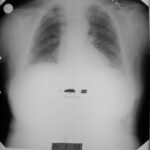

1992 - İlk Başvuru

Sol göğüs ağrısı ve öksürük şikâyeti. Çok düşkün halde.

Malign lenfoma (plevral biyopsi)

Röntgende belirgin düzelme. Tümör tamamen kayboldu.

Röntgende belirgin düzelme görüldü. Tedaviye devam edildi.

Tümörün tamamen kaybolduğu görüldü.